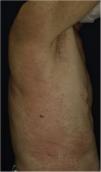

A 73-year-old male with unresectable head and neck squamous cell carcinoma was treated with monthly pembrolizumab (200 mg). He had no family or personal history of skin disease, including psoriasis. Soon after the second administration, he developed itchy erythema, which spread to the trunk and extremities. Physical examination showed coalesced erythema and papulaes on the trunk and extremities (Fig. 1). Histopathological examination showed vacuolar changes of the basement membrane of the epidermis and prominent infiltration of eosinophils in the upper dermis (Fig. 2). Because grade of cutaneous Immune-Related Adverse Events (irAEs) was 2, pembrolizumab was continued under treatment with topical corticosteroid; however, itchy erythema gradually worsened, and after 5 doses pembrolizumab was discontinued. Oral prednisolone was administered at a dose of 5‒10 mg/day, but the skin lesions further worsened and a different skin rash appeared. One month after discontinuing pembrolizumab, infiltrative erythematous and slightly keratotic plaques were observed on the trunk and extremities (Fig. 3). Mucous involvement was not observed. A second biopsy revealed subcorneal neutrophilic abscess, individual cell keratinization, liquefaction degeneration of the basement membrane region and dermal cellular infiltrates containing eosinophils (Fig. 4). After increasing the dose of oral prednisolone to 30 mg/day for 2 weeks, the skin lesions improved. After prednisone discontinuation, there was no recurrence of skin lesions.

The present case initially developed a maculopapular or morbiliform coalesced erythema on the trunk and extremities 5 weeks after initiation of pembrolizumab. Initial biopsy specimen showed interface changes of the epidermis and dermis junction, and prominent eosinophil infiltration in the upper dermis. Because pembrolizumab was effective for SCC, pembrolizumab was continued thereafter using topical corticosteroid, but itchy erythema was gradually worsened, and pembrolizumab was stopped after 5 doses. His rash was treated with oral prednisolone (initially 5 mg/day for 1 week, and 10 mg/day for another 1 week); however, 2 months later, his skin rash deteriorated, and clinical phenotype changed along with the gradual worsening of the skin rash. Of interest, the second biopsy revealed psoriasiform changes such as subcorneal neutrophilic abscess, while individual epidermal cell keratinization and liquefaction degeneration were also observed.